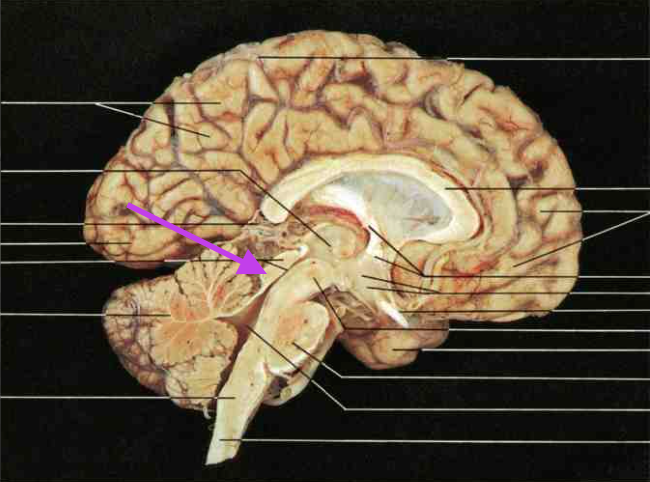

Frontal Lobe. Section is Cerebrum and diencephalon

Central Sulcus. Section is Cerebrum and diencephalon

Parietal Lobe. Section is Cerebrum and diencephalon

Temporal Lobe. Section is Cerebrum and diencephalon

Occipital Lobe. Section is Cerebrum and diencephalon

Lateral Sulcus (fissure). Section is Cerebrum and diencephalon

Longitudinal Fissure. Section is Cerebrum and diencephalon

Precentral Gyrus. Section is Cerebrum and diencephalon

Postcentral Gyrus. Section is Cerebrum and diencephalon

Corpus callosum. Section is Cerebrum and diencephalon

Thalamus and Third Ventricle. Section is Cerebrum and diencephalon

Hypothalamus. Section is Cerebrum and diencephalon